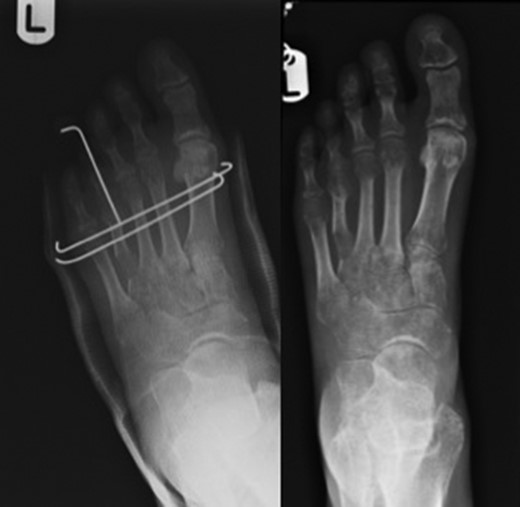

Brachymetatarsia is defined as one metatarsal ending 5 mm or more proximal to the parabolic arch of the other adjacent metatarsals [1, 2]. A shortened metatarsus can be congenital (Fig. 1) or acquired through trauma, infections, tumours or iatrogenic.

Pre-operative images on the left alongside x-rays on the right depicting congenitally short fourth toes.